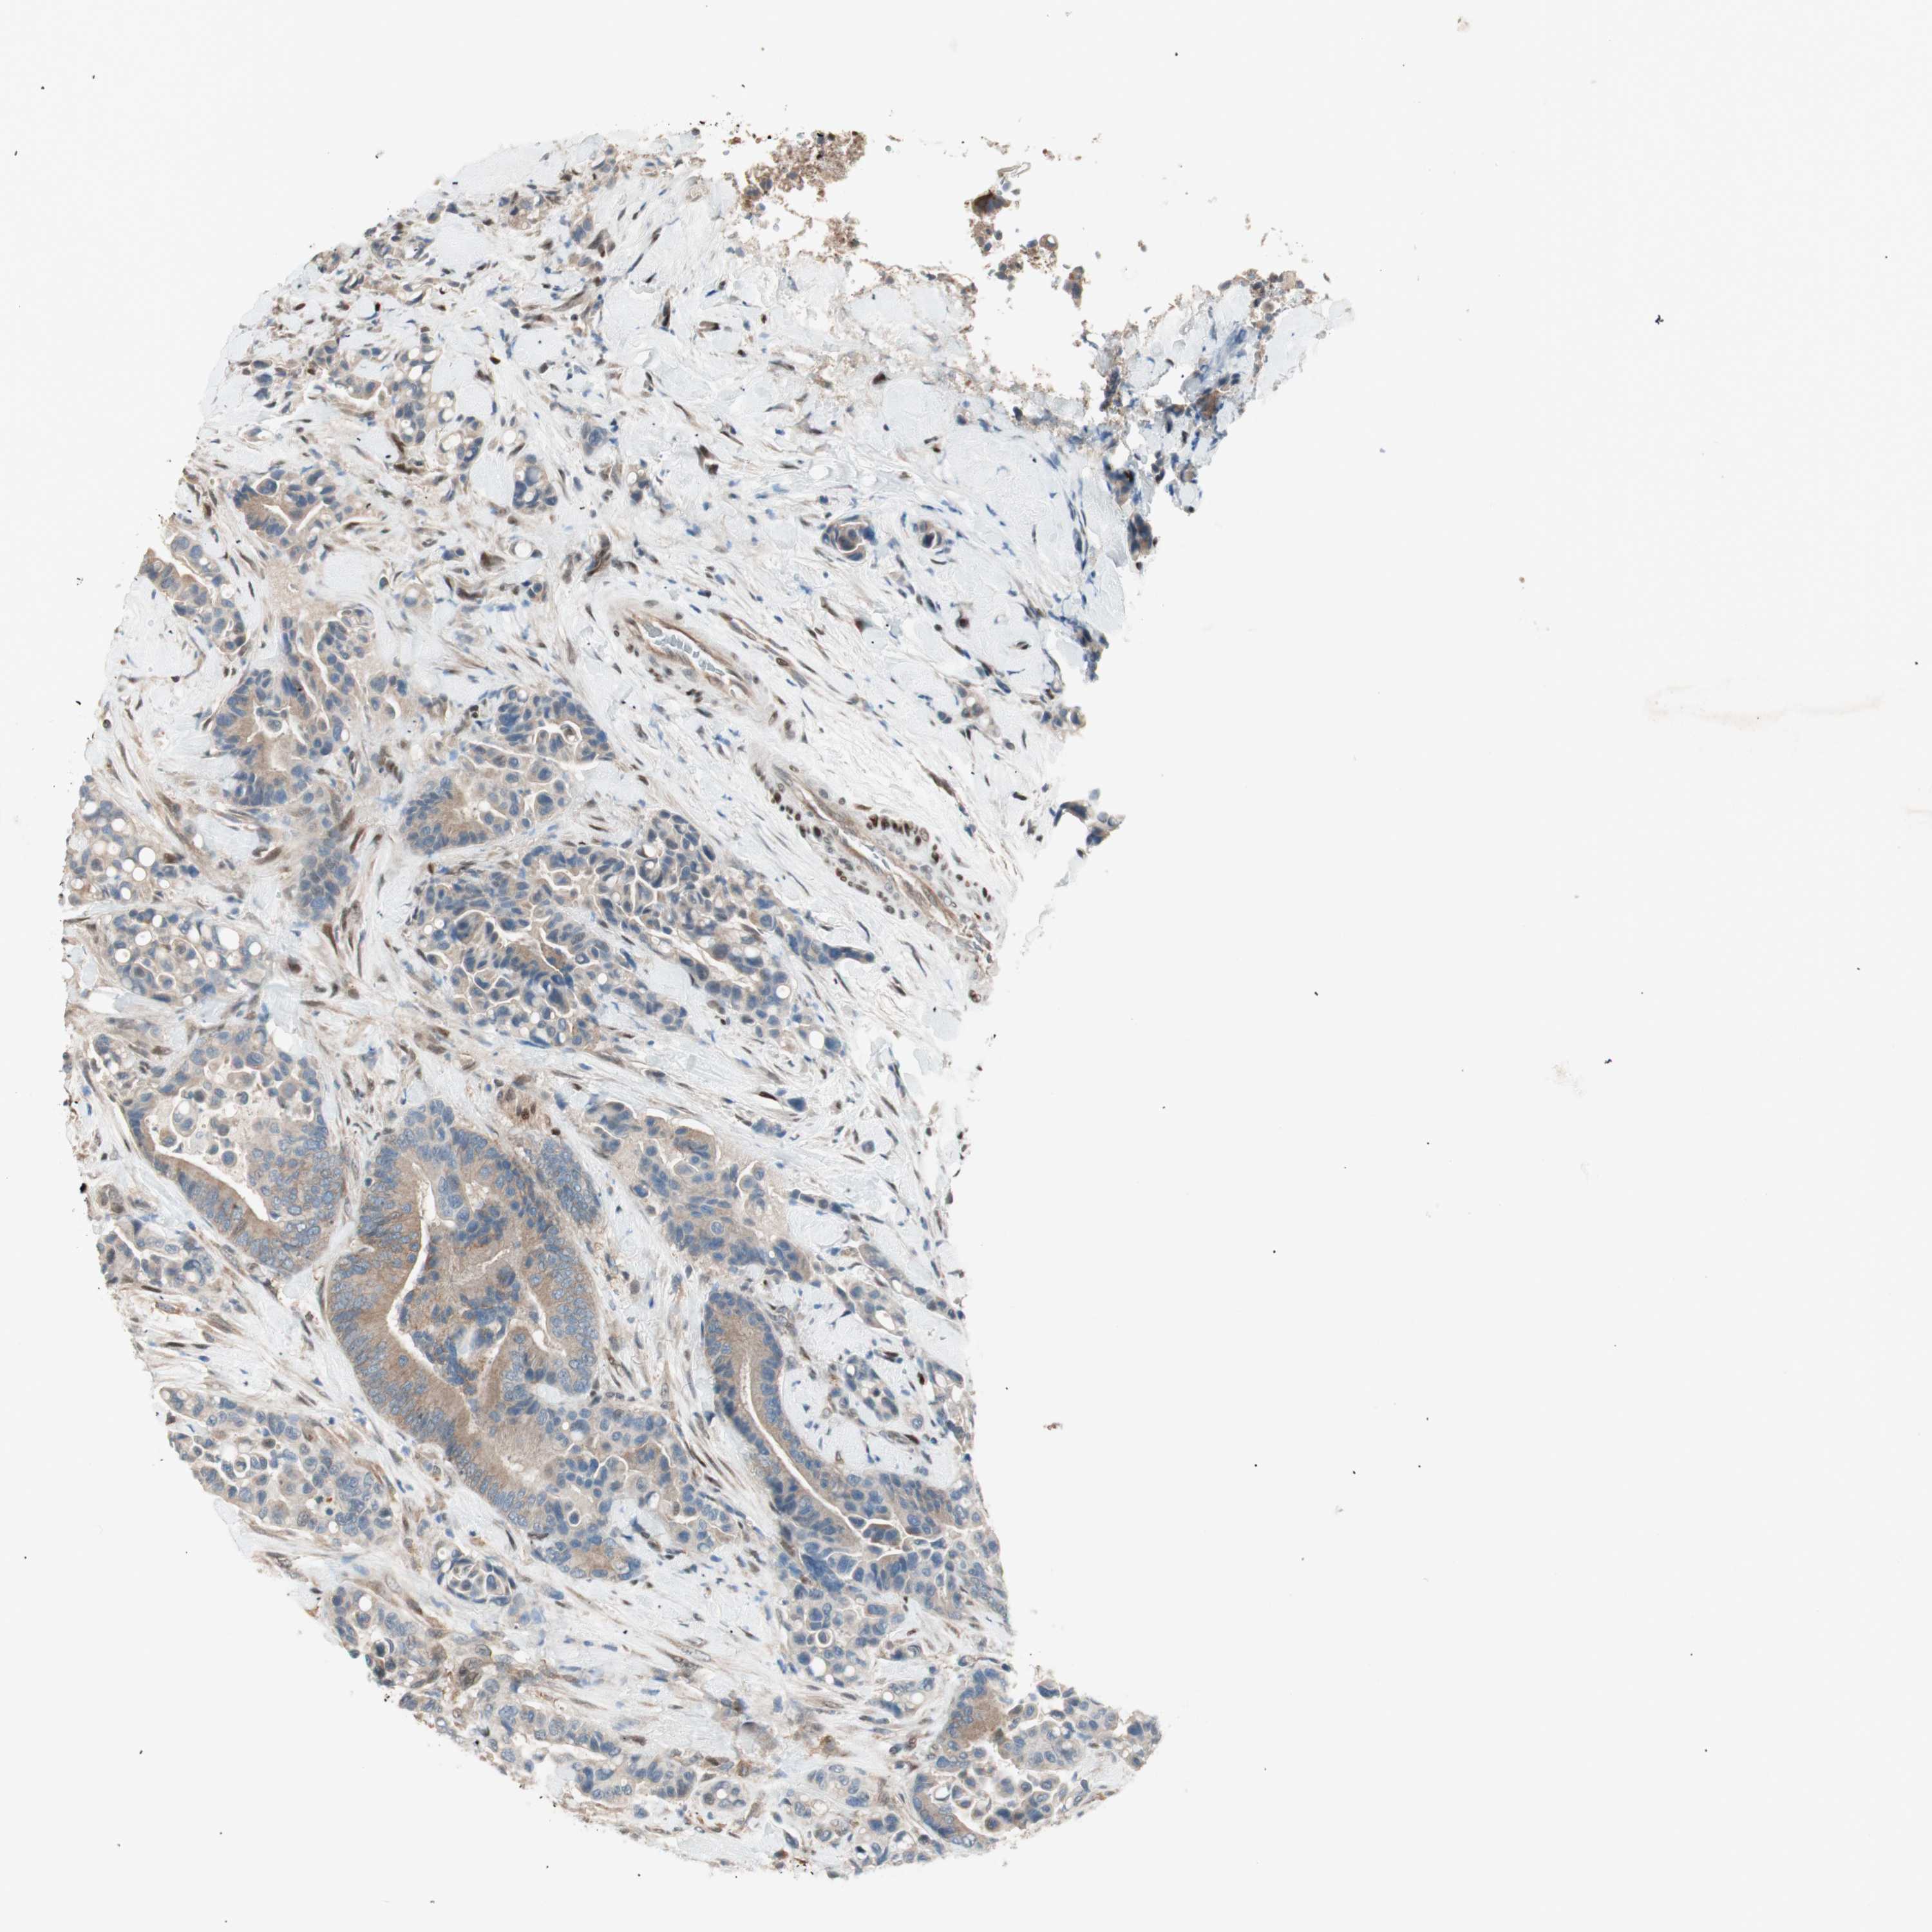

CANCER COLORECTAL CANCER Show tissue menu

COAD TCGA COAD VALIDATION READ TCGA READ VALIDATION PROTEIN COAD CPTAC PROTEIN EXPRESSION

ANTIBODIES

AND

VALIDATION